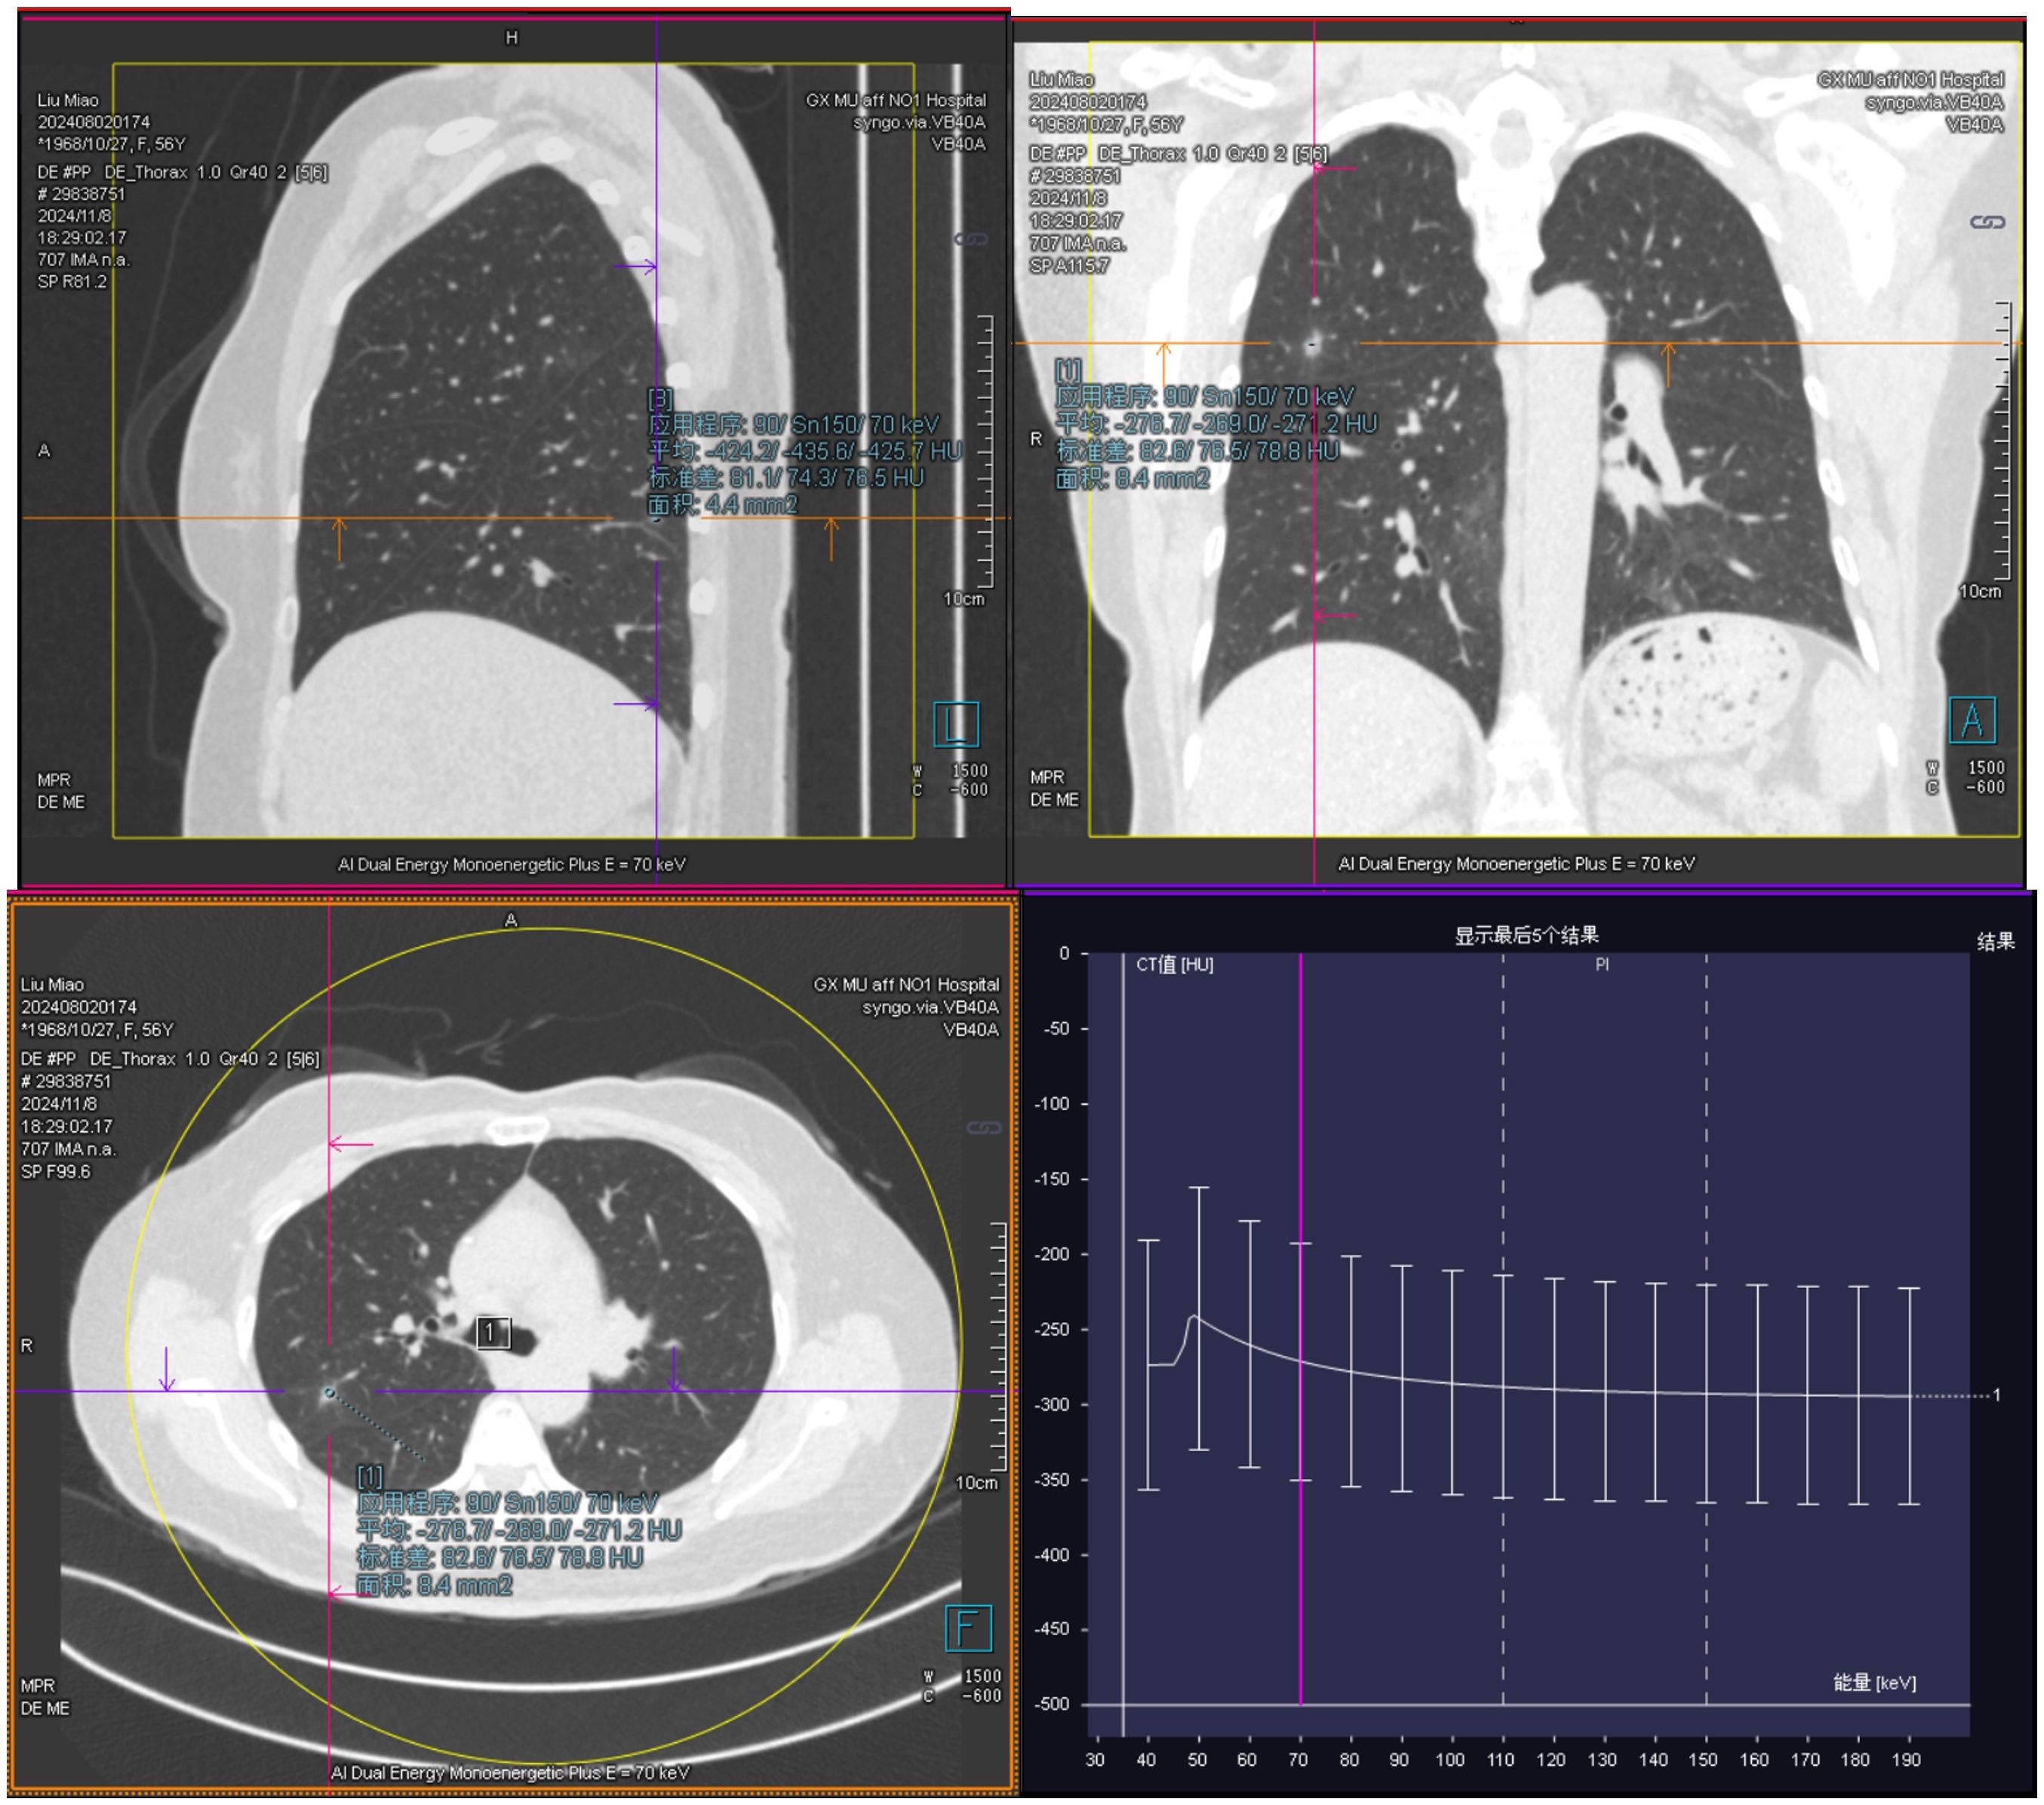

Background: Dedifferentiated liposarcoma (DDLPS) is a relatively common type of liposarcoma, typically occurring in the retroperitoneum and limbs. It is rarely found in the female reproductive system, leading to the absence of a standard treatment protocol for primary ovarian dedifferentiated liposarcoma. This case presents a personal experience-based approach, as there is a lack of standard treatment guidelines, relying on treatment consensus for more common locations and decades of clinical experience. Case Presentation: This case report describes a 55-year-old woman who was admitted due to a gradually enlarging mass in the right lower abdomen, accompanied by bloating and abdominal pain. Physical examination revealed a palpable abdominal mass. Gynecological ultrasound showed a hyperechoic mass measuring 135*128*91mm in the pelvic-abdominal cavity. CT imaging suggested a large cystic and solid mixed liposarcoma originating from the ovary, with unclear delineation of the uterine fundus and slight compression of surrounding organs. Pelvic MRI revealed an irregular mass approximately 10.7cm×12.6cm×12.2cm, with slightly prolonged T1 and heterogeneous T2 signals, showing fat signal in the right fatty tissue, suggesting invasion of the uterine wall by liposarcoma. The patient then underwent open surgery, and postoperative pathology with immunohistochemistry confirmed dedifferentiated liposarcoma. FISH testing was positive for MDM2, confirming the diagnosis of ovarian-origin dedifferentiated liposarcoma. Although the patient refused chemotherapy, she has been followed up every three months, and the current follow-up shows no signs of tumor recurrence. Conclusion: Ovarian dedifferentiated liposarcoma is an extremely rare condition, with surgery being the preferred treatment method. This report presents a rare case of ovarian dedifferentiated liposarcoma, providing a reference for clinical diagnosis and treatment. Through collaboration between gynecology, pathology, and imaging departments, the accuracy of the diagnosis and comprehensiveness of treatment were ensured. Long-term follow-up of the patient provided valuable insights into the recurrence and prognosis of the disease.